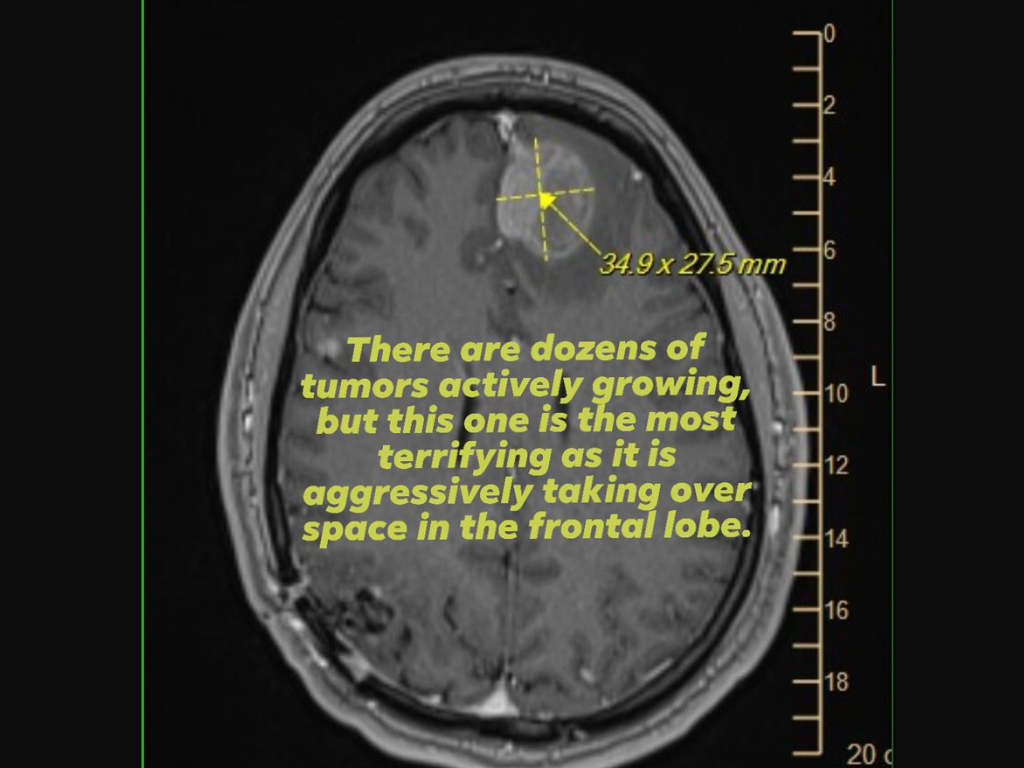

Kanıt olarak, işten çıkarmalarla ilgili kilit kararları veren Epic Games yöneticilerinden destek veya yardım isterken, ön lobda agresif bir tümör olduğunu gösteren bir beyin taraması (MRI) görüntüsünü de ekledi.